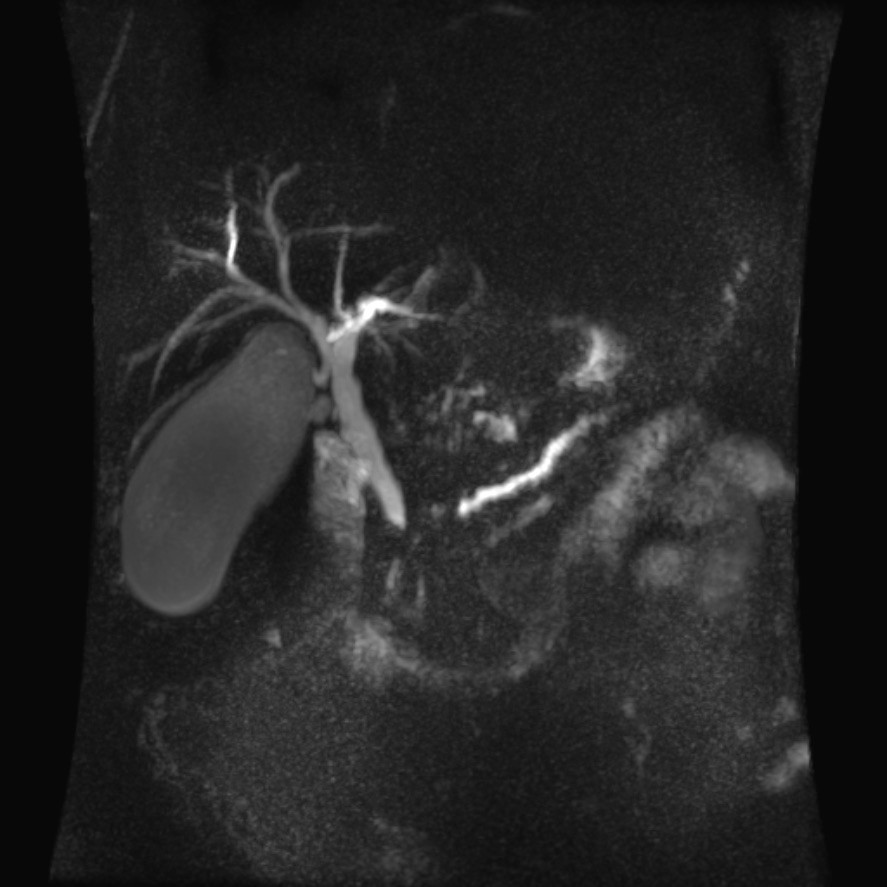

Colangioresonancia